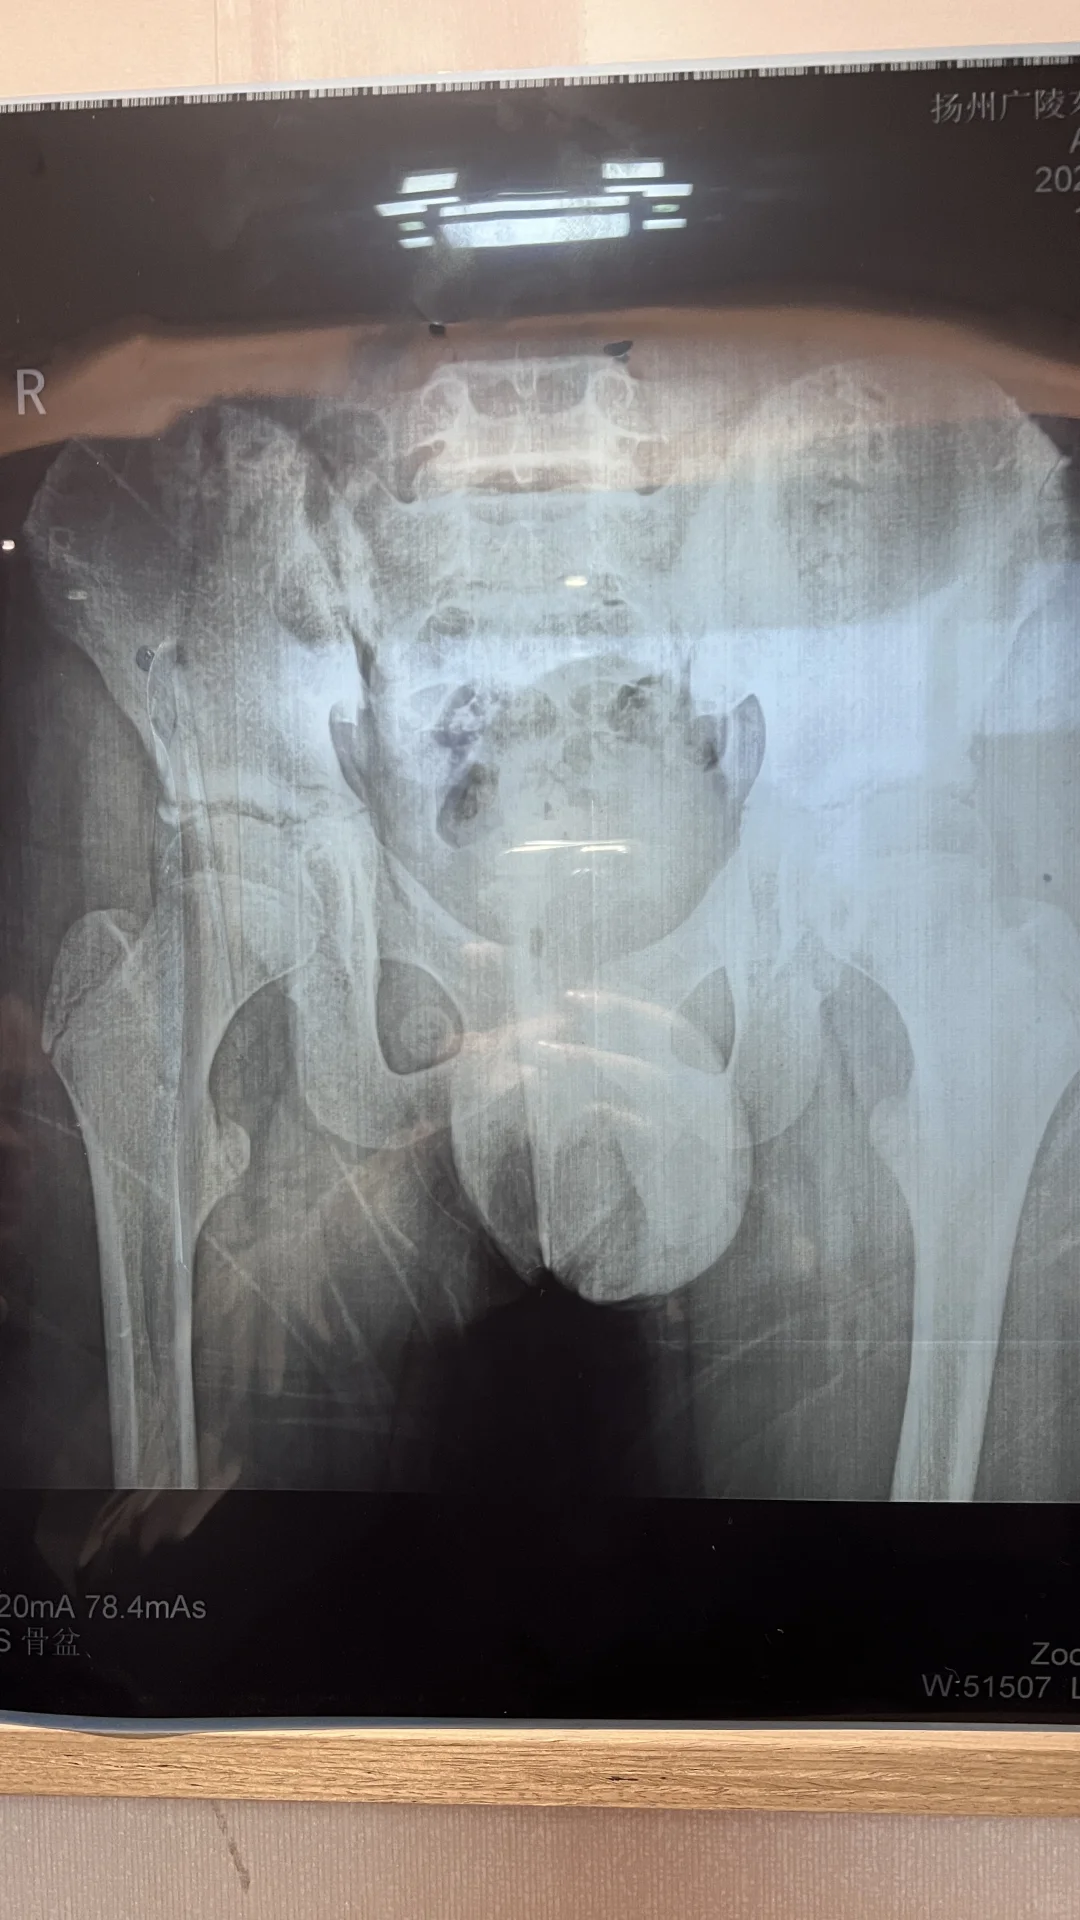

孩子六岁半,有没有先髋,严重吗?